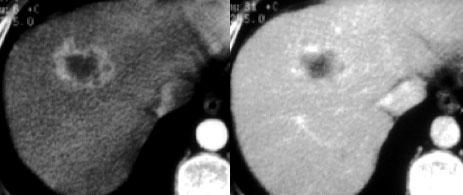

TRÁI: Ngấm thuốc dạng viền trong di căn ung thư vú. PHẢI: Ngấm thuốc dạng nốt không liên tục trong u máu.

Ngấm thuốc ngoại vi

Sự ngấm thuốc của u máu bắt đầu từ ngoại vi.

Đặc điểm ngấm thuốc có dạng nốt hoặc dạng cầu và không liên tục.

Ngấm thuốc dạng viền là ngấm thuốc ngoại vi liên tục và không bao giờ là u máu.

Ngấm thuốc dạng viền là đặc điểm của các tổn thương ác tính, đặc biệt là di căn.